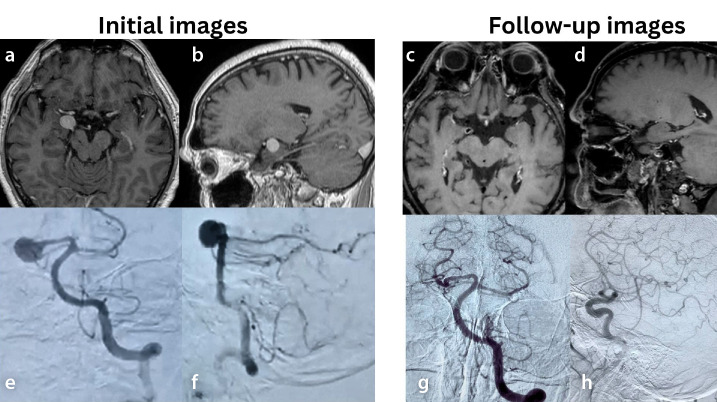

Purpose: The use of flow diverter (FD) stents is continually expanding. Aneurysms on arterial bifurcation typically have an undesirable anatomical form, are frequently wide-necked, and include one or more side-branch arteries. In recent years, the off-label use of flow diversion in treating intracranial aneurysms beyond the internal carotid artery has become increasingly popular. This study reports our center's initial experience treating bifurcation aneurysms with FD devices, documenting occlusion outcomes using the O'Kelly-Marotta and modified Cekirge-Saatci scales, as well as the safety of FD usage in bifurcation locations.

Methods: This retrospective, single-center study analyzed a prospectively maintained database of patients with cerebral aneurysms treated endovascularly. The study identified bifurcation aneurysms that were treated between January 2019 and May 2022 by placing an FD device covering the neck of the aneurysm.

Results: Our short series suggests that flow diversion is a viable therapeutic option for bifurcation aneurysms with favorable angiographic outcomes.

Conclusion: In highly selective cases, flow diversion may be considered for treating bifurcation aneurysms in patients who will undergo follow-up examinations in the future.

Clinical significance: Flow diversion has emerged as a valuable technique in the management of bifurcation aneurysms, offering the potential for satisfactory occlusion and long-term outcomes.